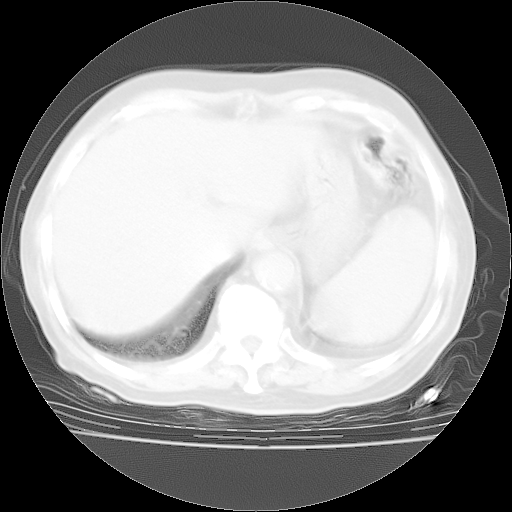

4月28日肺部CT——再次出现类似去年5月9日——透光度降低,“间质性”改变。

4月28日肺部CT——再次出现类似去年5月9日——磨玻璃样、间有“粟粒样”改变。

4月28日肺部CT

个人阅读4.14日肺部CT平扫:纵隔窗无异常,但肺窗示:双下肺内、后基底段有片絮状侵润影,部位以后基底段为著,以间质改变为主,呈急性肺泡炎征像,和首次住院影像学有相似之处。仅是个人读片,明日请相关专家再读片哈。其它建议同上。

1、108#的是4月14日的胸部CT(发此贴时还没看着28日的CT)。14日的胸部CT其实已经出现改变(如108#所述),个人认为28日的胸部CT除纵膈窗疑似有双侧胸膜增厚或少量胸积液(可行胸部B超明确)外,与4月14日对照病变有所加重;2、已经给予“异烟肼、利福平、乙胺丁醇”抗痨治疗?如果是,甲强龙80mg可缓慢减量;如果环磷酰胺已停用,暂不使用;3、中性粒细胞92%,明显升高,目前体温情况?注意合并细菌感染可能,使用左氧氟沙星情况下,是否联用B-内酰胺类抗菌药物?另外是查免疫全套非风湿全套。

今请临免主任会诊后认为:4月14日胸部CT已有双下肺间质性改变。患者病情复发多系激素减量过快不正规所致。目前甲强龙80mg/日,一周后酌情开始减量,不易过快。环磷酰胺若已停用,暂不使用。他同意目前抗菌药物使用,但应考虑是否加用B-内酰胺类抗菌药物(中性细胞明显增高);2、结核复发目前依据不足;3、若免疫全套各项指标正常,考虑多系特发性肺间质炎可能大。4、加强支持,并注意保护胃黏膜。

今上午去请教了临免、呼吸主任:1、介绍病史和阅读系列胸部CT一致认为:患者肺结核不考虑,仍为肺间质纤维化,目前处于急性肺泡炎阶段。2、若仍发热,可将甲强龙增至:80mg Bid静滴,同时鉴于中性增高,合并细菌感染可能,继续左氧氟沙星治疗,再联用B-内酰胺抗菌药物,如头孢哌酮--舒巴坦;3、停用抗痨药;4、目前甲强龙每日剂量160mg ,体温正常后再酌情减量;目前暂不用免疫抑制剂;4、不建议使用免疫增强剂等;5、加强支持治疗,鼓励患者进食;5、注意随访肝、肾功及血常规情况;6、因患者目前激素用量较大,加用胃黏膜保护剂,防止消化道出血可能。